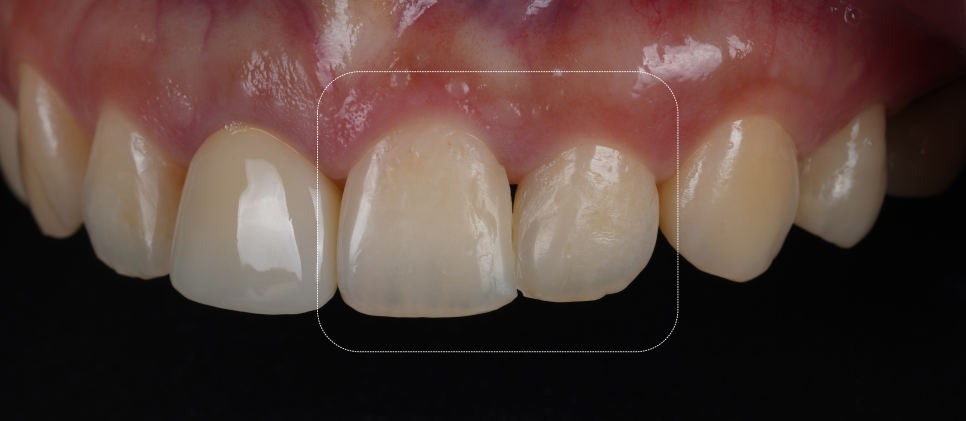

입 천장 쪽에서 확인한 모습

촬영일 : 251023

기존 레진을 다 제거한 뒤 접착층을 만들고 치아색과 투명도가 비슷한 레진을 여러 층으로 쌓았어요.

한 층 붙이고 굳히고 또 붙이고 굳히고.... 정성스레 겹겹이 쌓아 공들여 작업해야 돼요.

완성 후에는 치아 경계가 사라지고 자연 채광에서 봐도 거친 부분 없이 매끄럽게 보였어요.

이전의 각진 부분도 사라졌죠.